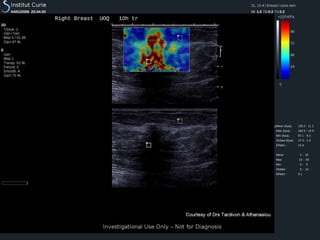

Axial and lateral deformations afteran axial constraint   Courtesy of Dr Anne Tardivon - Institut Curie - Paris Static Elastography

Static Elastography